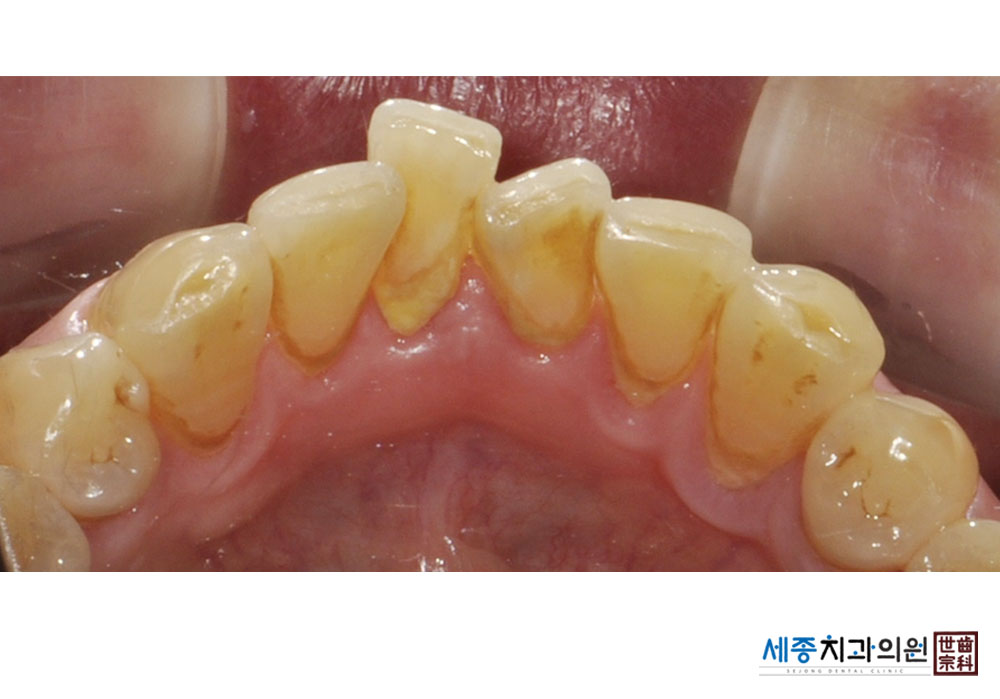

[스케일링] 치주질환 예방 스케일링

치료전 : 2023-01-17

가글마취&저주파 스켈러를 사용한 착색제거 스케일링